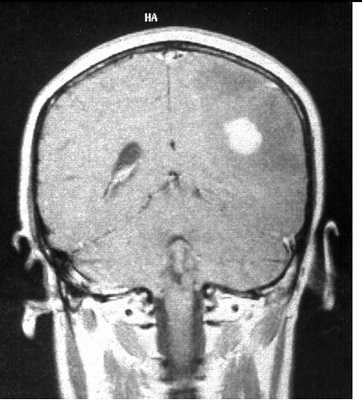

МРТ головного мозга. Анапластическая астроцитома. Корональные Т2-зависимая МРТ и Т1-зависимая МРТ с контрастированием.

МРТ головного мозга. Множественная анапластическая астроцитома (стрелки). Сагиттальная Т1-зависимая МРТ с контрастированием.